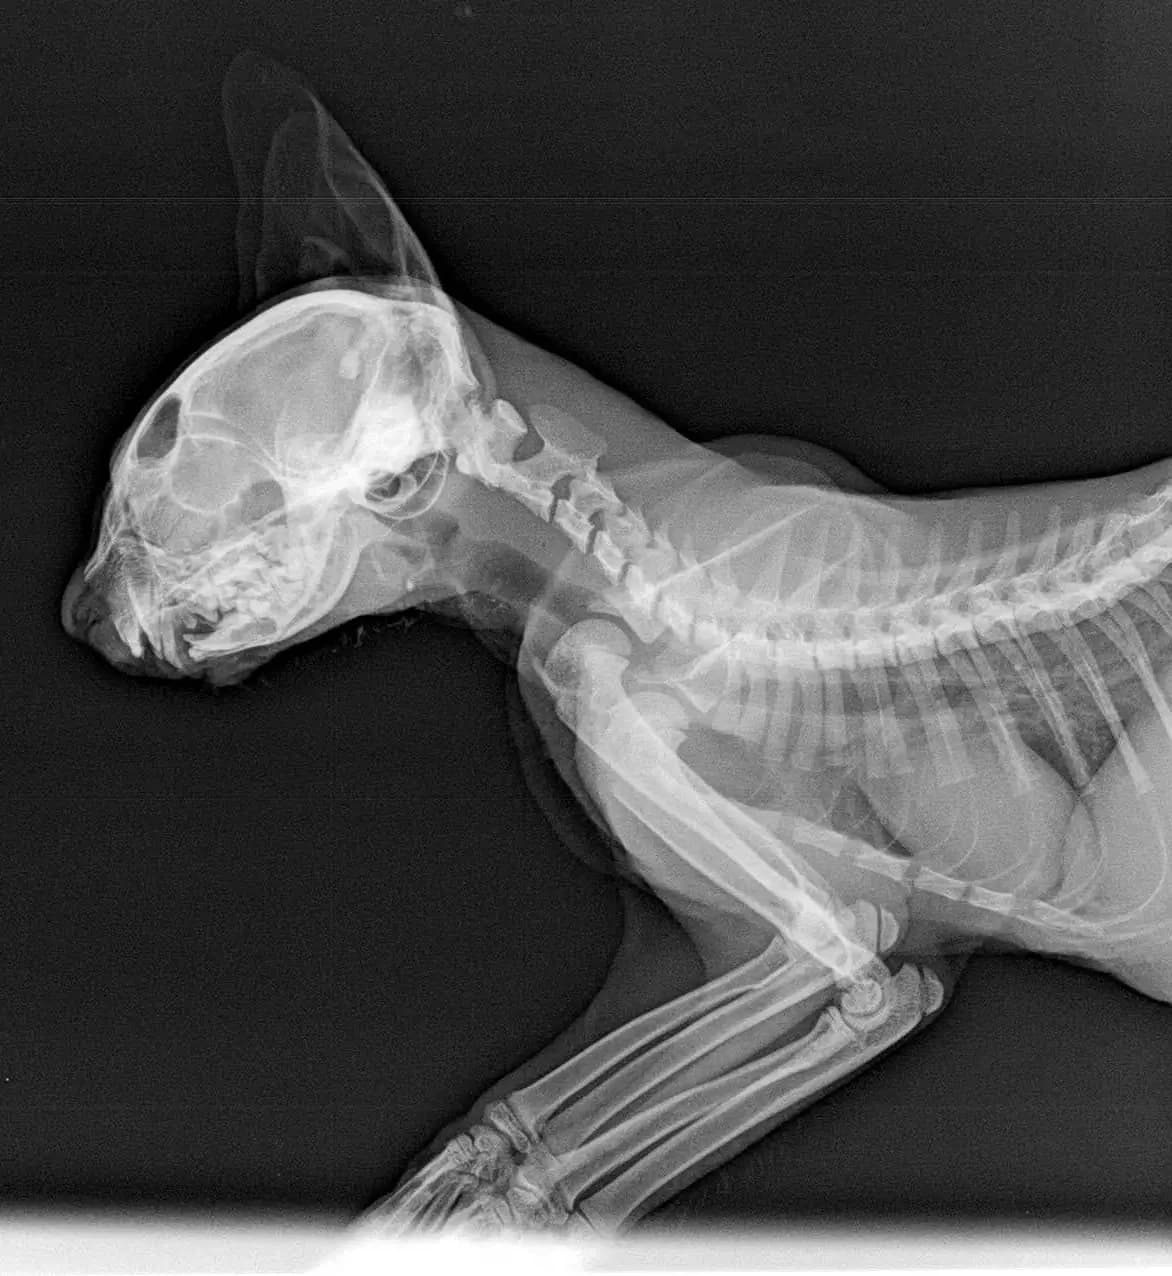

Anfang Mai 2025 wurde Jamiro von unseren griechischen Tierschutzfreundinnen H. & I. auf Andros in einem schlimmen Zustand eingefangen. Er konnte seine Kiefer nicht bewegen und daher auch nicht richtig fressen. At the beginning of May 2025, Jamiro was captured in a terrible condition on Andros by our Greek animal welfare friends H. & I. He couldn't move his jaws and therefore couldn't eat properly. Da die diagnostischen und medizinischen Möglichkeiten für solche Fälle auf Andros nicht gegeben sind, sandten sie den Kleinen nach Rücksprache mit uns zu einer Tierärztin nach Athen, mit der wir bei komplizierteren Behandlungen zusammenarbeiten. Sie röntgte ihn und stellte eine Deformation fest, die Jamiro daran hindert, seine Kiefer zu öffnen und zu fressen. Since the diagnostic and medical resources for such cases are lacking on Andros, after consulting with us, they sent the little one to a veterinarian in Athens with whom we work together for more complex treatments. She x-rayed him and discovered a deformity that prevents Jamiro from opening his jaws and eating. Wir suchten gemeinsam nach einem Spezialisten für Kieferchirurgie und fanden aufgrund eines Hinweises einer Bekannten in Athen jemanden, der sich des Falls annahm. Dieser Spezialist hat natürlich eine entsprechende Praxisausstattung und untersuchte Jamiro gründlich. Together, we searched for a specialist in oral surgery and, thanks to a tip from a friend in Athens, found someone who took on the case. This specialist, of course, has the appropriate equipment and examined Jamiro thoroughly. Er teilte uns mit, dass Jamiro einen alten Bruch im Kiefergelenk hat und beide Gelenke blockiert sind. Er meint, dass die Katze eine einseitige Gnathektomie benötigt, also eine operative Entfernung eines Teils des Kiefers. Er denkt, dass dies ausreicht und dass eine beidseitige Gnathektomie nicht notwendig sein wird. Die Prognose bei einer solchen Operationen ist sehr gut, Jamiro wird wieder normal und sch